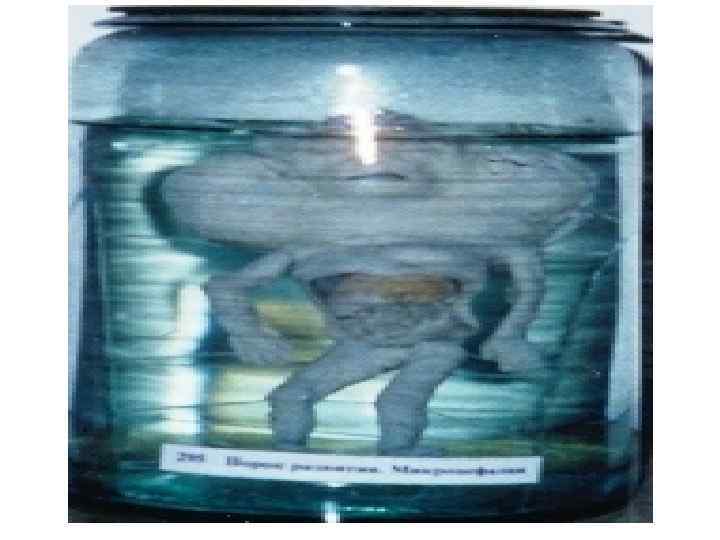

Омыртқалардың дамуының варианттары және аномалиялары 1 -омыртқалардың доғасының аномалиялары: -оң және сол жақ доғалардың біркіпеуі -доғалардың омыртқа денесімен бірікпеуі -омыртқа доғасының жетілмеуі немесе оның жоқ болуы 2 -омыртқалардың өсінділердің аномалиялары: -қосымша өсінділер -қылқан өсінділерінің бөліктенуі -буын өсінділерінің жетілмеуі және деформациясы 3 -омыртқалардың денесінің деформациясы 4 -омыртқалардың әрбір бөліктеріндегі, олардың сандары не көбейіп, не азайып өзгеруі • 5 -люмбализация • 6 -сакрализация • 7 -омырқалардың көптеген синостоздары • • •

8 -сколиоз 9 -омыртқалардың доғаларының бірікпеуі 10—спондилез Атавистикалық белгілер: 1 -күрең тәрізді тері өсіндісі 2 -құйымшақ омыртқаларының көп болуы 3 -күрең тәрізді өсінділер. Олар жұмсақ тіндерден тұрады да, терімен жабылады. Адам қартайған кезде омыртқалар омыртқа арасындағы дискалардың және олардың пішіндері өзгеруіне байланысты қозғаласы нашарлайды: олар серпінділігін жоғалтып үлкен кеуде қисығын түзеді – кәрілік қисығы.